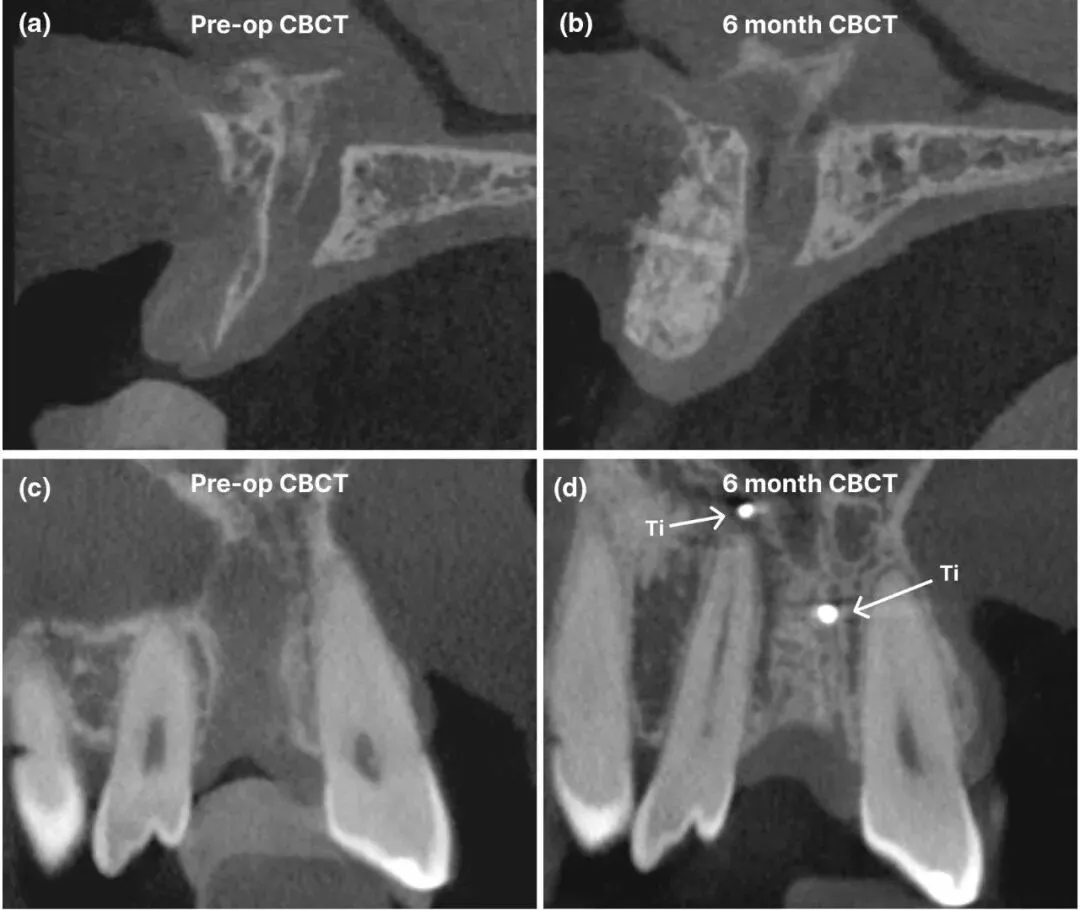

二期(术后6个月):CBCT 复查骨再生良好,支架部分降解,植入种植体(初期稳定性佳);愈合后安装牙冠完成修复。

图5 引导骨再生术前与愈合6个月后的影像学对比[(a)和(c)术前矢状面和冠状面横截面;(b)和(d)术后6个月矢状面和冠状面横截面]

1.骨再生效果:术后 6 个月骨体积增量达 364.69±2.53mm³,骨缺损基本修复;新骨在支架晶格内形成骨桥,与健康骨整合良好,种植体植入位置误差仅毫米级(颈部冠方偏差 1.08mm,根尖偏差 1.24mm)。